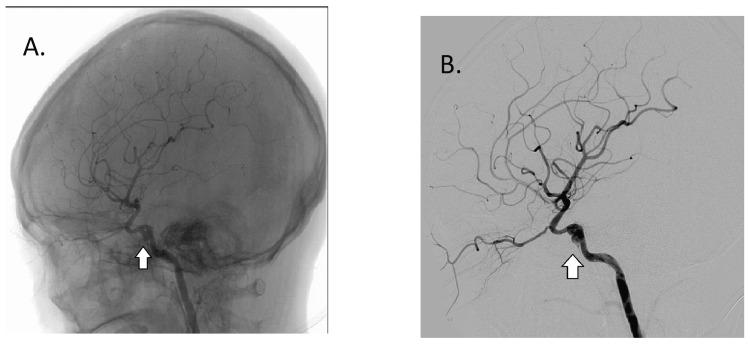

We report a rare case of a missed intracavernous internal carotid artery dissecting aneurysm occurring as a complication of the base of skull fracture with severe brain injury causing acute cavernous sinus syndrome with permanent vision loss. A 31-year-old Myanmar lady had an alleged motor vehicle accident and suffered severe traumatic brain injury with multiple intracranial bleeds, multiple facial bone and base of skull fractures, and limb fractures. At one week post-trauma, she had severe right eye proptosis with vision loss, ophthalmoplegia, chemosis, and high intraocular pressure. She was suspected clinically to have a traumatic cavernous carotid fistula and a lateral canthotomy and cantholysis was performed. The patient was scheduled for an embolization of the fistula but during cerebral digital subtraction angiography, a dissecting aneurysm instead was noted at the right internal carotid artery at the cavernous segment. A cerebral computed tomography angiography and venography showed right cavernous sinus and right superior ophthalmic vein thrombosis. The patient was started on antiplatelet agents and underwent successful stenting-assisted coiling of the aneurysm, and her right eye proptosis gradually resolved. While awaiting definitive treatment of the aneurysm, the patient had severe exposure keratopathy and despite intensive hydration and antimicrobial treatment, it later developed into a fungal corneal ulcer. A temporary tarsorrhaphy was done and the ulcer gradually healed into a significant corneal scar and the final visual acuity of her right eye was no light perception. The underlying cause of cavernous sinus syndrome is diverse and unique. A thorough assessment and appropriate neuroimaging should be performed to arrive at the proper diagnosis in a timely manner. This is in order to prevent delays in the definitive treatment and irreversible ocular morbidity.

摘要

我们报告了一例罕见的漏诊海绵窦段颈内动脉夹层动脉瘤,它是颅骨骨折合并严重脑损伤的并发症,导致急性海绵窦综合征并造成永久性视力丧失。一名31岁的缅甸女性据称遭遇机动车事故,患有严重的创伤性脑损伤,伴有多处颅内出血、多根面骨和颅骨骨折以及四肢骨折。创伤后一周,她出现严重的右眼突出伴视力丧失、眼球运动麻痹、结膜水肿和高眼压。临床怀疑她患有外伤性海绵窦瘘,并进行了外眦切开术和眦部松解术。患者原计划进行瘘管栓塞,但在脑数字减影血管造影时,发现右侧海绵窦段颈内动脉有一个夹层动脉瘤。脑部计算机断层扫描血管造影和静脉造影显示右侧海绵窦和右侧眼上静脉血栓形成。患者开始使用抗血小板药物,并成功接受了动脉瘤支架辅助弹簧圈栓塞术,右眼突出逐渐消退。在等待动脉瘤的确定性治疗期间,患者出现严重的暴露性角膜病变,尽管进行了大量补液和抗菌治疗,但后来发展为真菌性角膜溃疡。进行了临时性睑裂缝合术,溃疡逐渐愈合形成明显的角膜瘢痕,右眼最终视力为无光感。海绵窦综合征的潜在病因多样且独特。应进行全面评估和适当的神经影像学检查,以便及时做出正确诊断。这是为了防止确定性治疗的延误和不可逆转的眼部疾病。